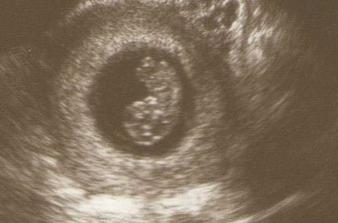

PM- 3.4., 2.5. jsem objevila dve carky. První potvrzení těhu 9.5.- na ultrazvuku jen bod, doktor mě pozval na kontrolu až 17., ale ja zmenila doktora, takže dalsi kontrola až 21.5...mimi už bylo vidět - 2 mm, tlouklo mu už "primitivní" srdíčko. Další kontrola 2.6. v 8 tt a 4 dnech - miminko bylo hezky vidět, je už 2,2 cm velké a dostala jsem krásnou fotku z UZV- je tam z profilu videt hlavicka. Další kontrola 26.6. - screening, odbery a downuv syndrom... Kontrola dopadla dobre, mimi ma ruce a nohy a vse je v normalu, uz ma 5, 3 cm! Je to maly akrobat.